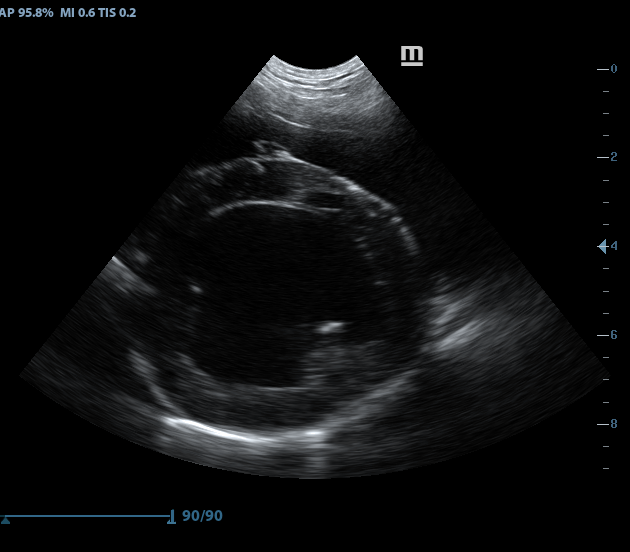

Images from the Magic P1